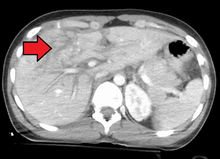

Imaging, such as the use of ultrasound or a computed tomography scan, is the generally preferred way of diagnosis as it is more accurate and is sensitive to bleeding, however; due to logistics this is not always possible.[4] For a person who is hemodynamically unstable a focused assessment with sonography for trauma (FAST) scan may take place which is used to find free floating fluid in the right upper quadrant and left lower quadrant of the abdomen. A physical examination may be used but is typically inaccurate in blunt trauma, unlike in penetrating trauma where the trajectory the projectile took can be followed digitally.[5] A diagnostic peritoneal lavage (DPL) may also be utilized but has limited application as it is hard to determine the origin of the bleeding.[6]